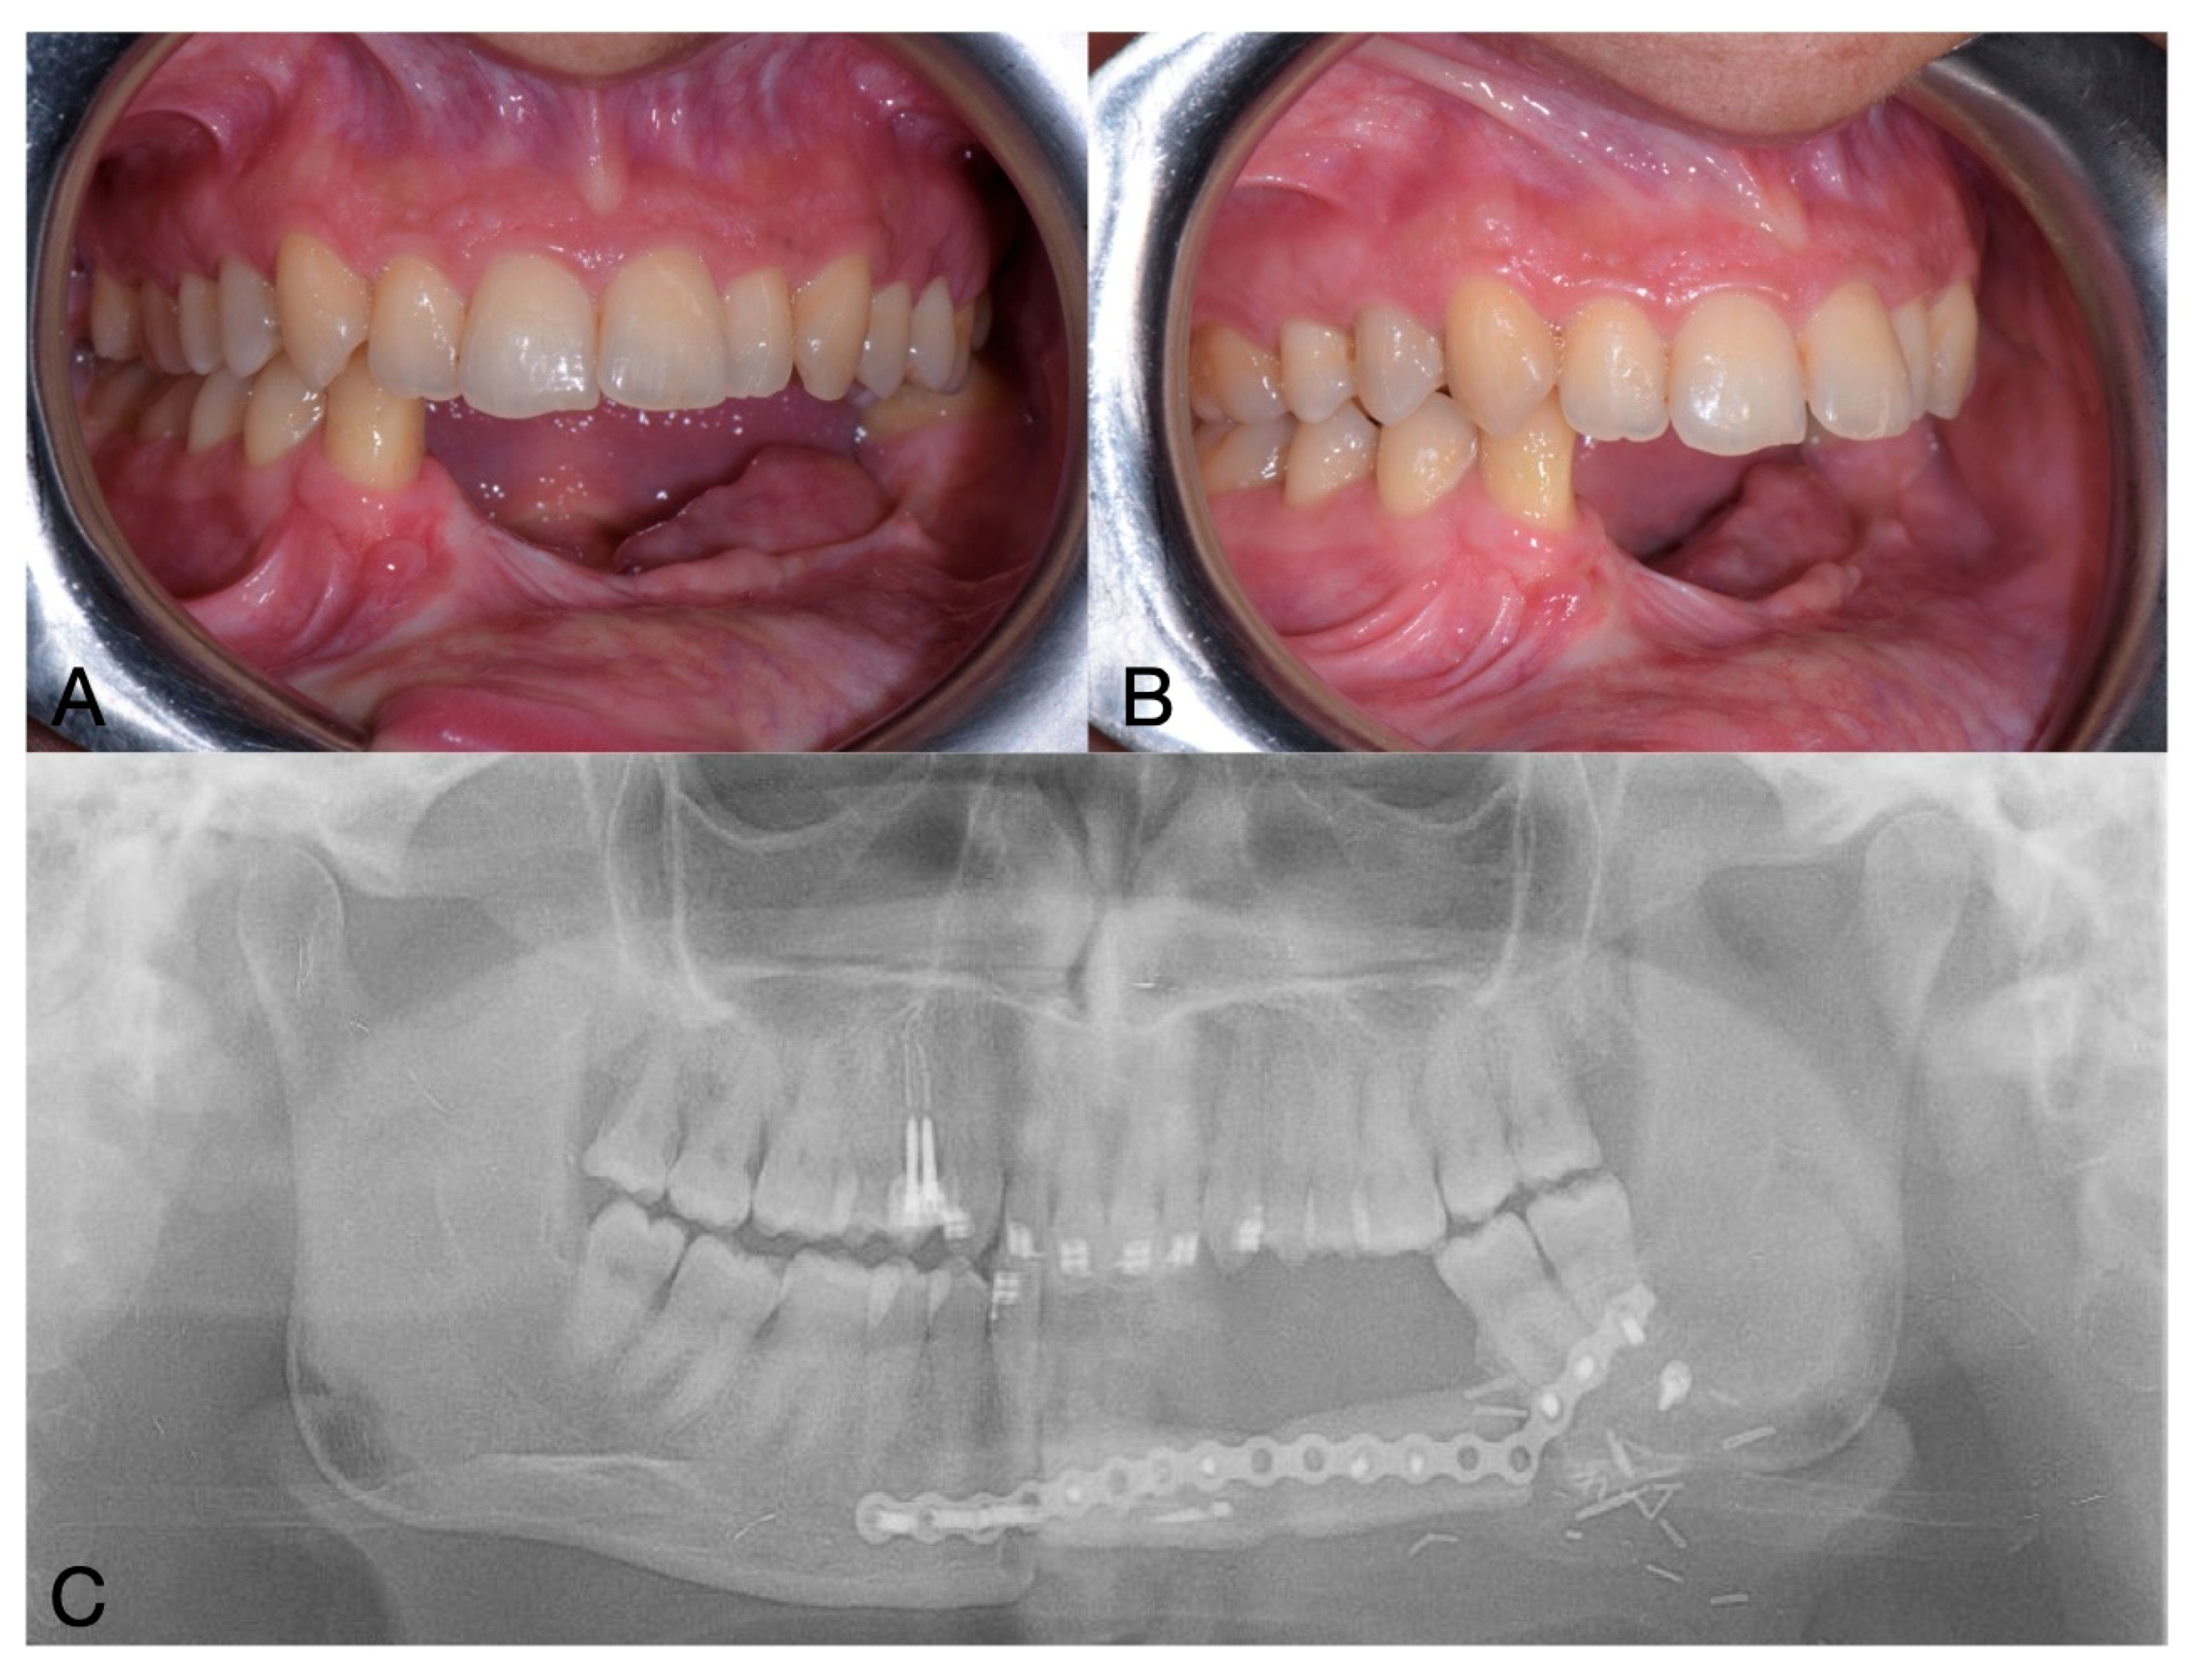

One year after the mandibular surgery, on OPG was performed to plan the subsequent implant-prosthetic rehabilitation (Figure 5).

Figure 5.

Pre-operative clinical situation (A,B) and OPG (C).

After a 3-month healing period, an OPG was performed, and implant uncovering and soft tissue surgery were planned (Figure 6).

Figure 6.

Postoperative OPG.

Figure 7.

Clinical (A,B) and radiographic (C) situation after prosthetic delivery.